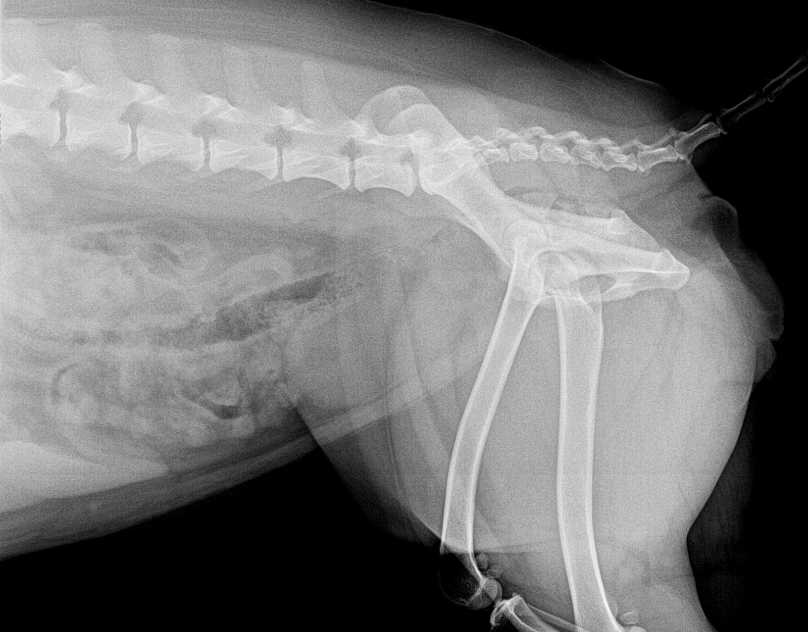

Atendemos casos de cojeras, fracturas, luxaciones, artrosis y lesiones articulares, tanto en animales adultos como en cachorros con alteraciones del desarrollo. Nuestro equipo de especialistas dispone de equipamiento de diagnóstico avanzado, como radiología digital, ecografía y endoscopia, que permite evaluar con precisión cada caso y planificar el tratamiento más adecuado.